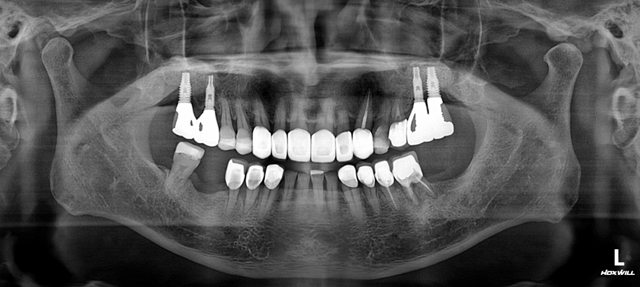

하악 다수치아 임플란트 보철.

Before

양측 어금니를 모두 임플란트 보철로 마무리 한 증례입니다.